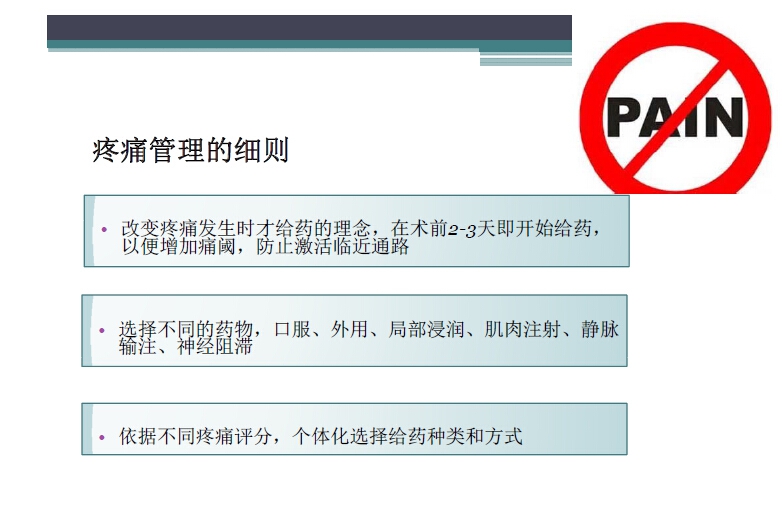

对于关节外科而言快速康复实际上是以病人加速舒适康复为目的,加强围术期的综合管理,包括疼痛和睡眠管理、血栓预防管理、感染预防管理、围术期血液管理,减少放置引流管、尿管、减少止血带应用,减少术后恶心呕吐,尽早进食,尽早康复等,逐步达到无血、无痛、无栓、无感、无肿、无管、无吐、无带等优良效果。为此,小编特邀王坤正教授等多位关节外科的专家参与撰写快速康复外科在关节外科的应用的主题文章,共话“人工关节置换快速康复”新理念,探讨建立符合我国特色的关节置换围手术期管理与快速康复体系,促进我国关节外科技术整体发展与提高。